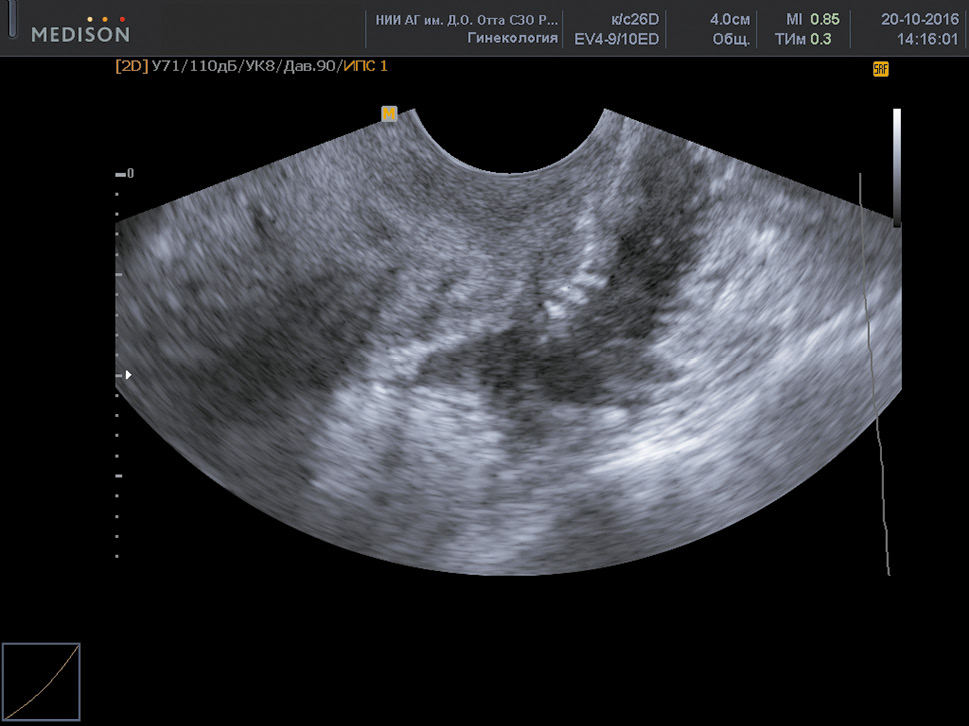

In most cases, cystic ovarian endometriosis had characteristic US signs, such as the location of the cyst behind and lateral to the uterus; medium and increased echogenicity of the “finely dispersed,” suspended material filling the cyst; and significant wall thickness (0.2–0.6 cm) (Fig. 1).

Fig. 1. Ovarian endometrioma

Рис. 1. Эндометриома яичника